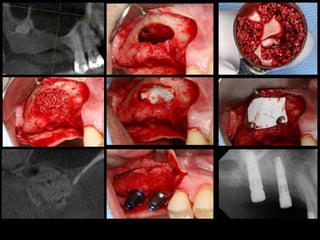

THE LATERAL WINDOW TECHNIQUE WITH A GRAFTING

MATERIAL AND SIMULTANEOUS OR DELAYED IMPLANT

INSTALLATION

• Tatum (mid-70s) afterwards described by boyne and james in 1980

• The maxillary sinus is exposed through oral mucosa in region of anterior, lateral

maxillary sinus wall.

• A midcrestal incision is made with posterior and anterior vertical releasing

incisions.

• A mucoperiosteal flap with trapezoid base - reflected exposing lateral wall of

sinus.

• A trapdoor osteotomy is performed on the lateral wall of sinus with burs or

piezoelectric surgery avoiding laceration of the schneiderian membrane.

• The trapdoor is infractured, schneiderian membrane is carefully dissected, elevated

from the floor, lateral, medial sinus wall.

• Displaced dorsocranially with blunt dissector to create a compartment for

placement of the graft.

• Implant placement simultaneously, if the height of the residual alveolar bone

provides sufficient primary stability.

• An implant bed is successively prepared with burs, implant tip exposed in the

created compartment in the maxillary sinus.

• The graft material is densely packed around the exposed implant surface to

facilitate de novo bone formation

• The lateral window covered by a resorbable collagen membrane to prevent

ingrowth of fibrous tissue before the mucoperiosteum is readapted and sutured.

• If stability is compromised, then the implants are inserted 4 to 12 months after the

augmentation.

• Final prosthetic solution is performed three to six months after implant

installation.